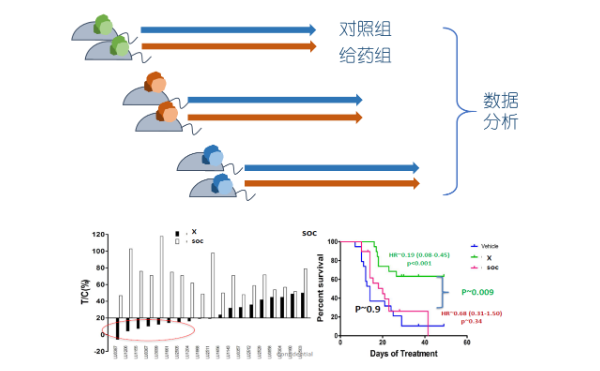

药效实验案例

● P1代肿瘤模型,早期即可以生长均匀

● 肿瘤模型生长均匀,实验稳定